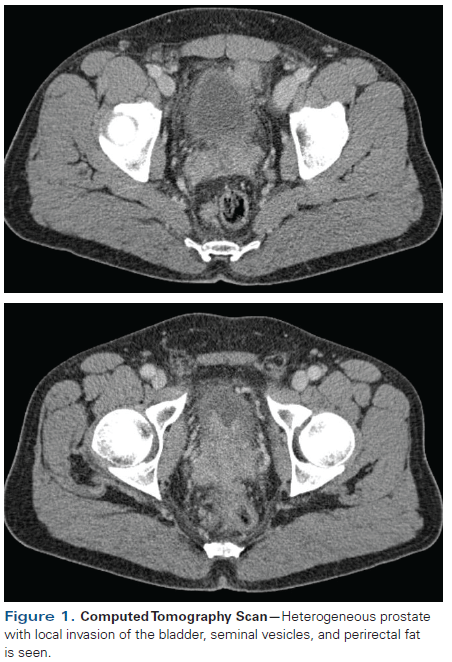

Figure 1. Computed Tomography Scan

Computed tomography (CT) performed in March 2015 for IMT surveillance showed a heterogeneous prostate with local invasion involving the bladder, seminal vesicles, and perirectal fat (Figure 1). His prostate-specific antigen (PSA) level was 22 ng/mL and digital rectal exam revealed a fixed prostate (cT4) not amenable to surgical resection. He underwent a third TURP in April 2015 for management of his lower urinary tract symptoms; this revealed adenocarcinoma of the prostate with Gleason score 4 + 3 = 7 (Figure 2). A staging bone scan revealed no evidence of metastatic disease. He was diagnosed with high-risk prostate cancer, and after discussion of his case in a multidisciplinary tumor board, external beam radiation therapy (EBRT) and androgen deprivation therapy (ADT) were prescribed. The patient asked whether chemotherapy would provide any additional benefit, given his young age. He is currently receiving ADT and radiation therapy (RT).